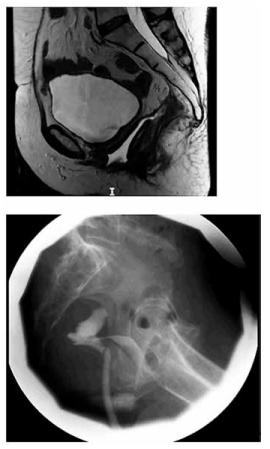

Paciente de 42 anos foi submetida a histerectomia total

e retossigmoidectomia laparoscópica com anastomose

mecânica por endometriose profunda. No terceiro dia de

pós-operatório, apresenta descarga de conteúdo fétido

pela vagina. Foi realizado estudo radiológico, apresentado a seguir:

Com base nas imagens e na cronologia do caso, qual é a causa mais provável dessa complicação?